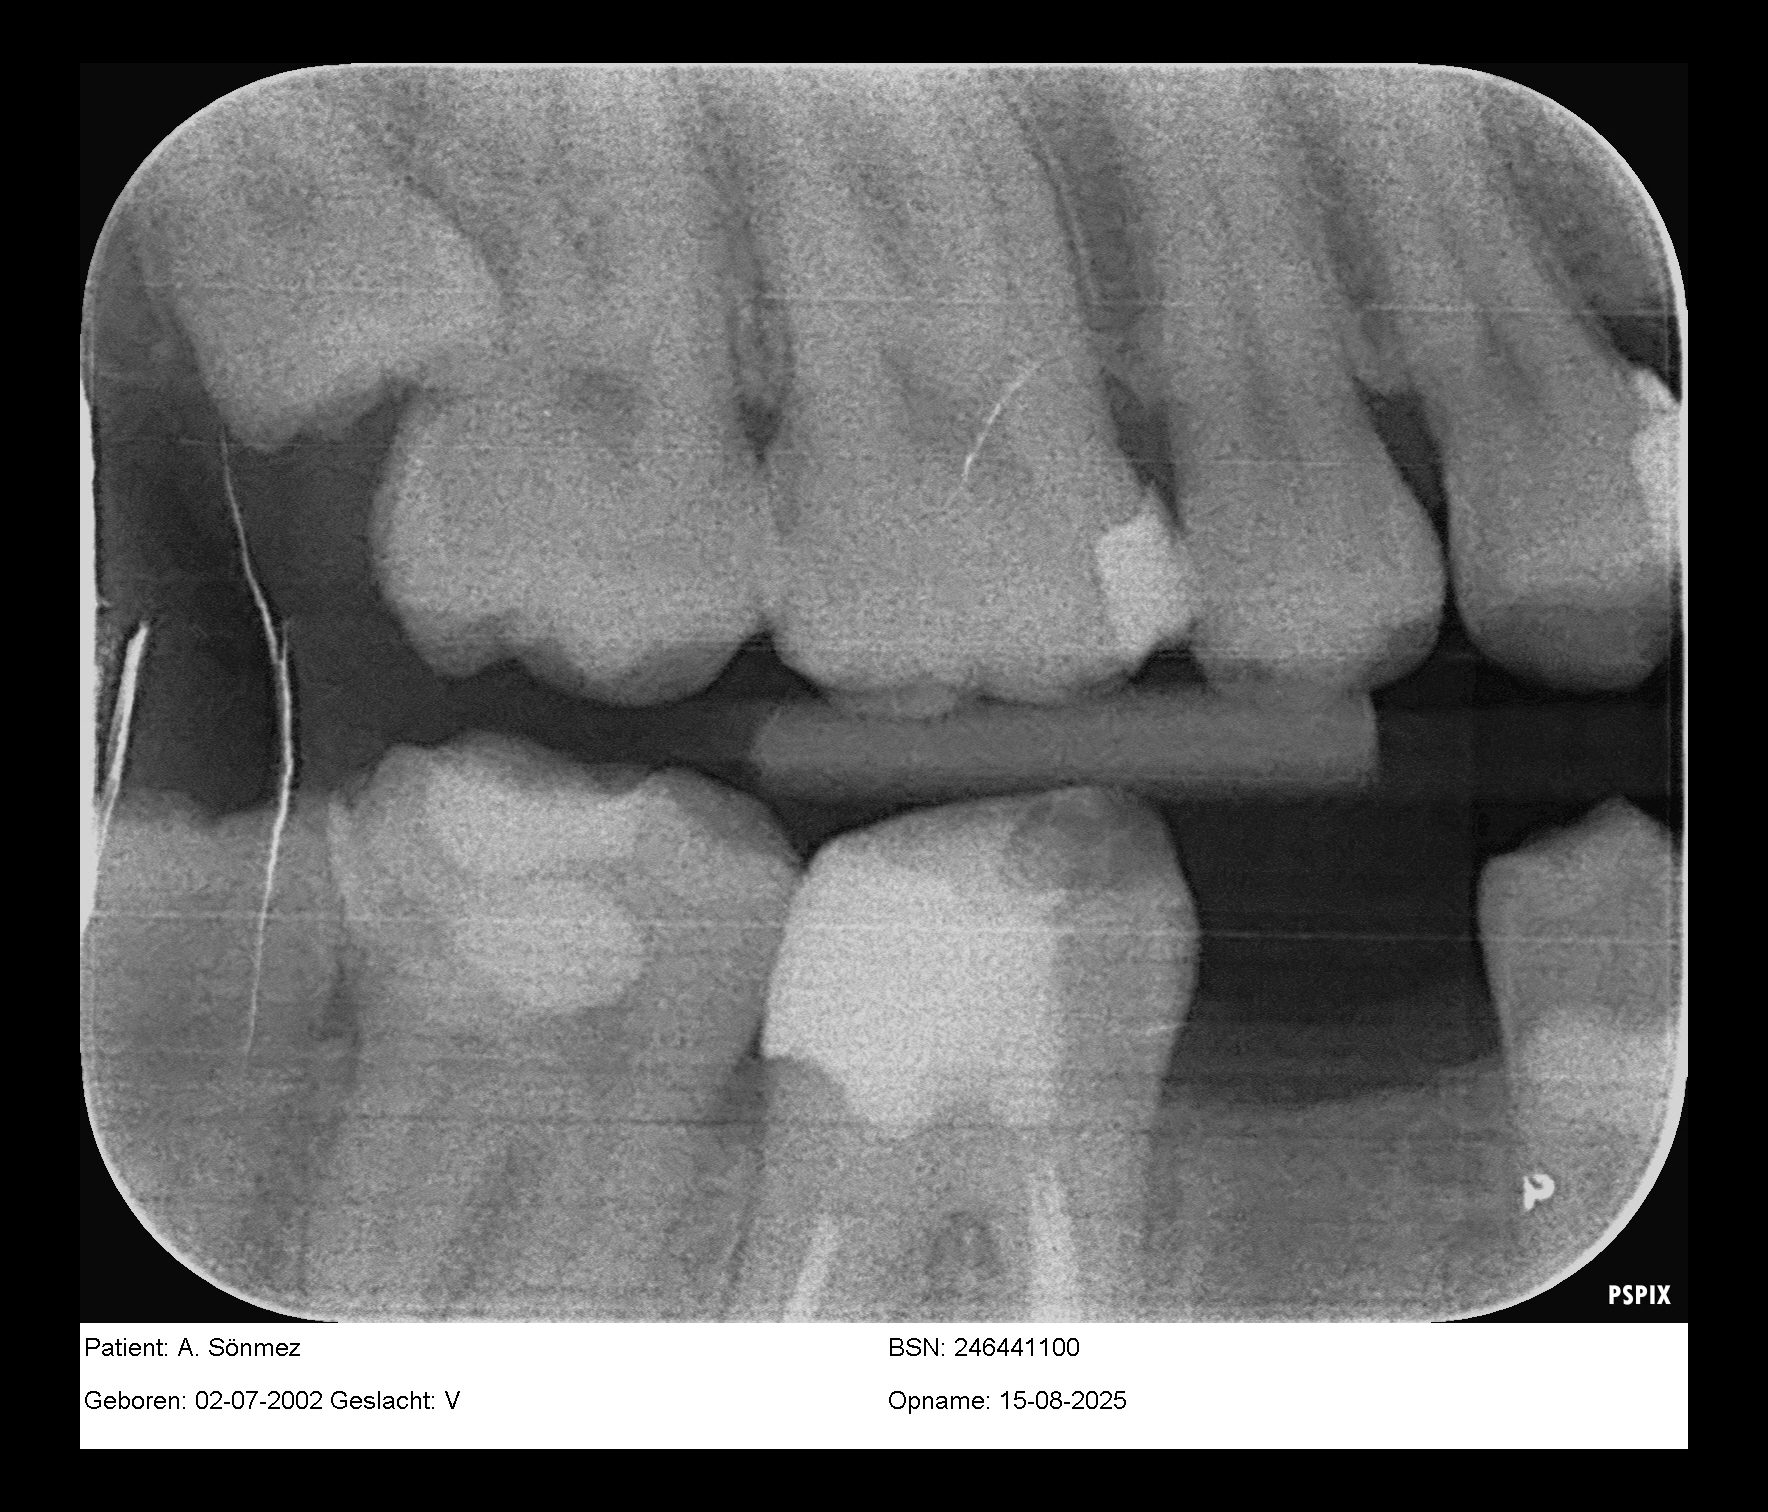

Dit zijn trouwens de foto's…

Dit zijn trouwens de foto's die vandaag zijn gemaakt!